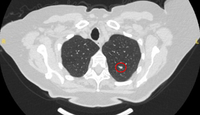

Computed tomography (CT) showing two areas (red circles) of mucoid impaction of the left upper lobe subsegmental bronchi, resulting in appearance that mimics a nodule

From the collection of Dr George Tsaknis, MD, PhD, FRCP(London), MRQA, MAcadMEd, PGCert; used with permission